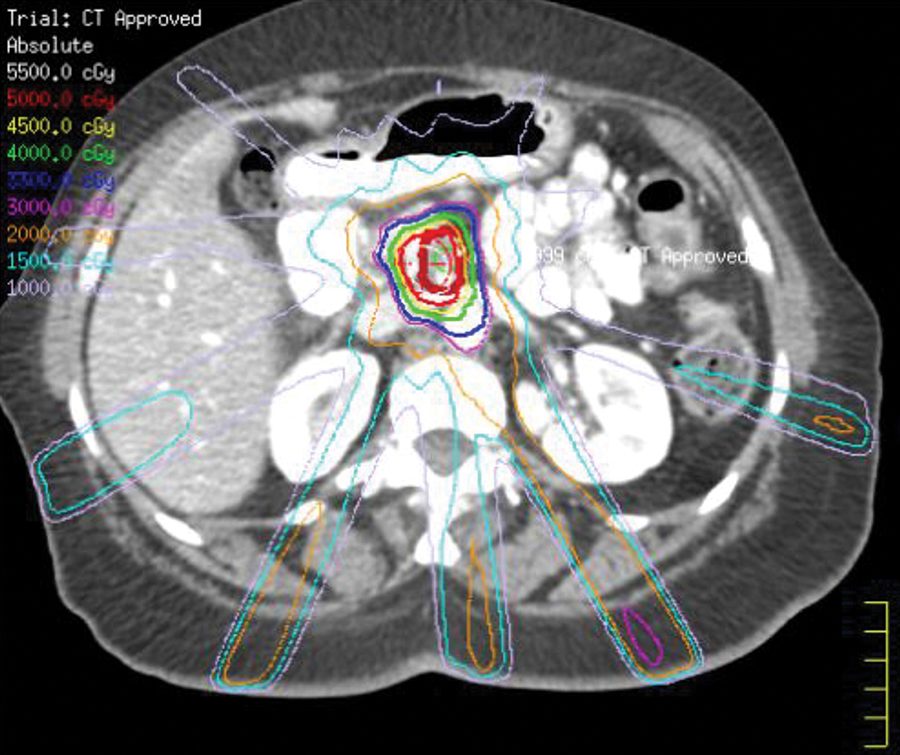

Mediante la cordotomía percutánea guiada por CT, primero se realiza una punción lumbar para inyectar un agente de radiocontraste en el líquido cefalorraquídeo para visualizar la médula espinal. Un cirujano usa, entonces, la técnica de CT en tiempo real para guiar el avance de una aguja en la médula espinal en la base del cráneo, y luego el avance de un electrodo de radiofrecuencia a través de la aguja para llegar al tracto espinotalámico. Una vez que se coloca correctamente, el electrodo se calienta para realizar la ablación de la vía del dolor en la médula espinal. El procedimiento se realiza con anestesia local para permitir la comunicación con el paciente.